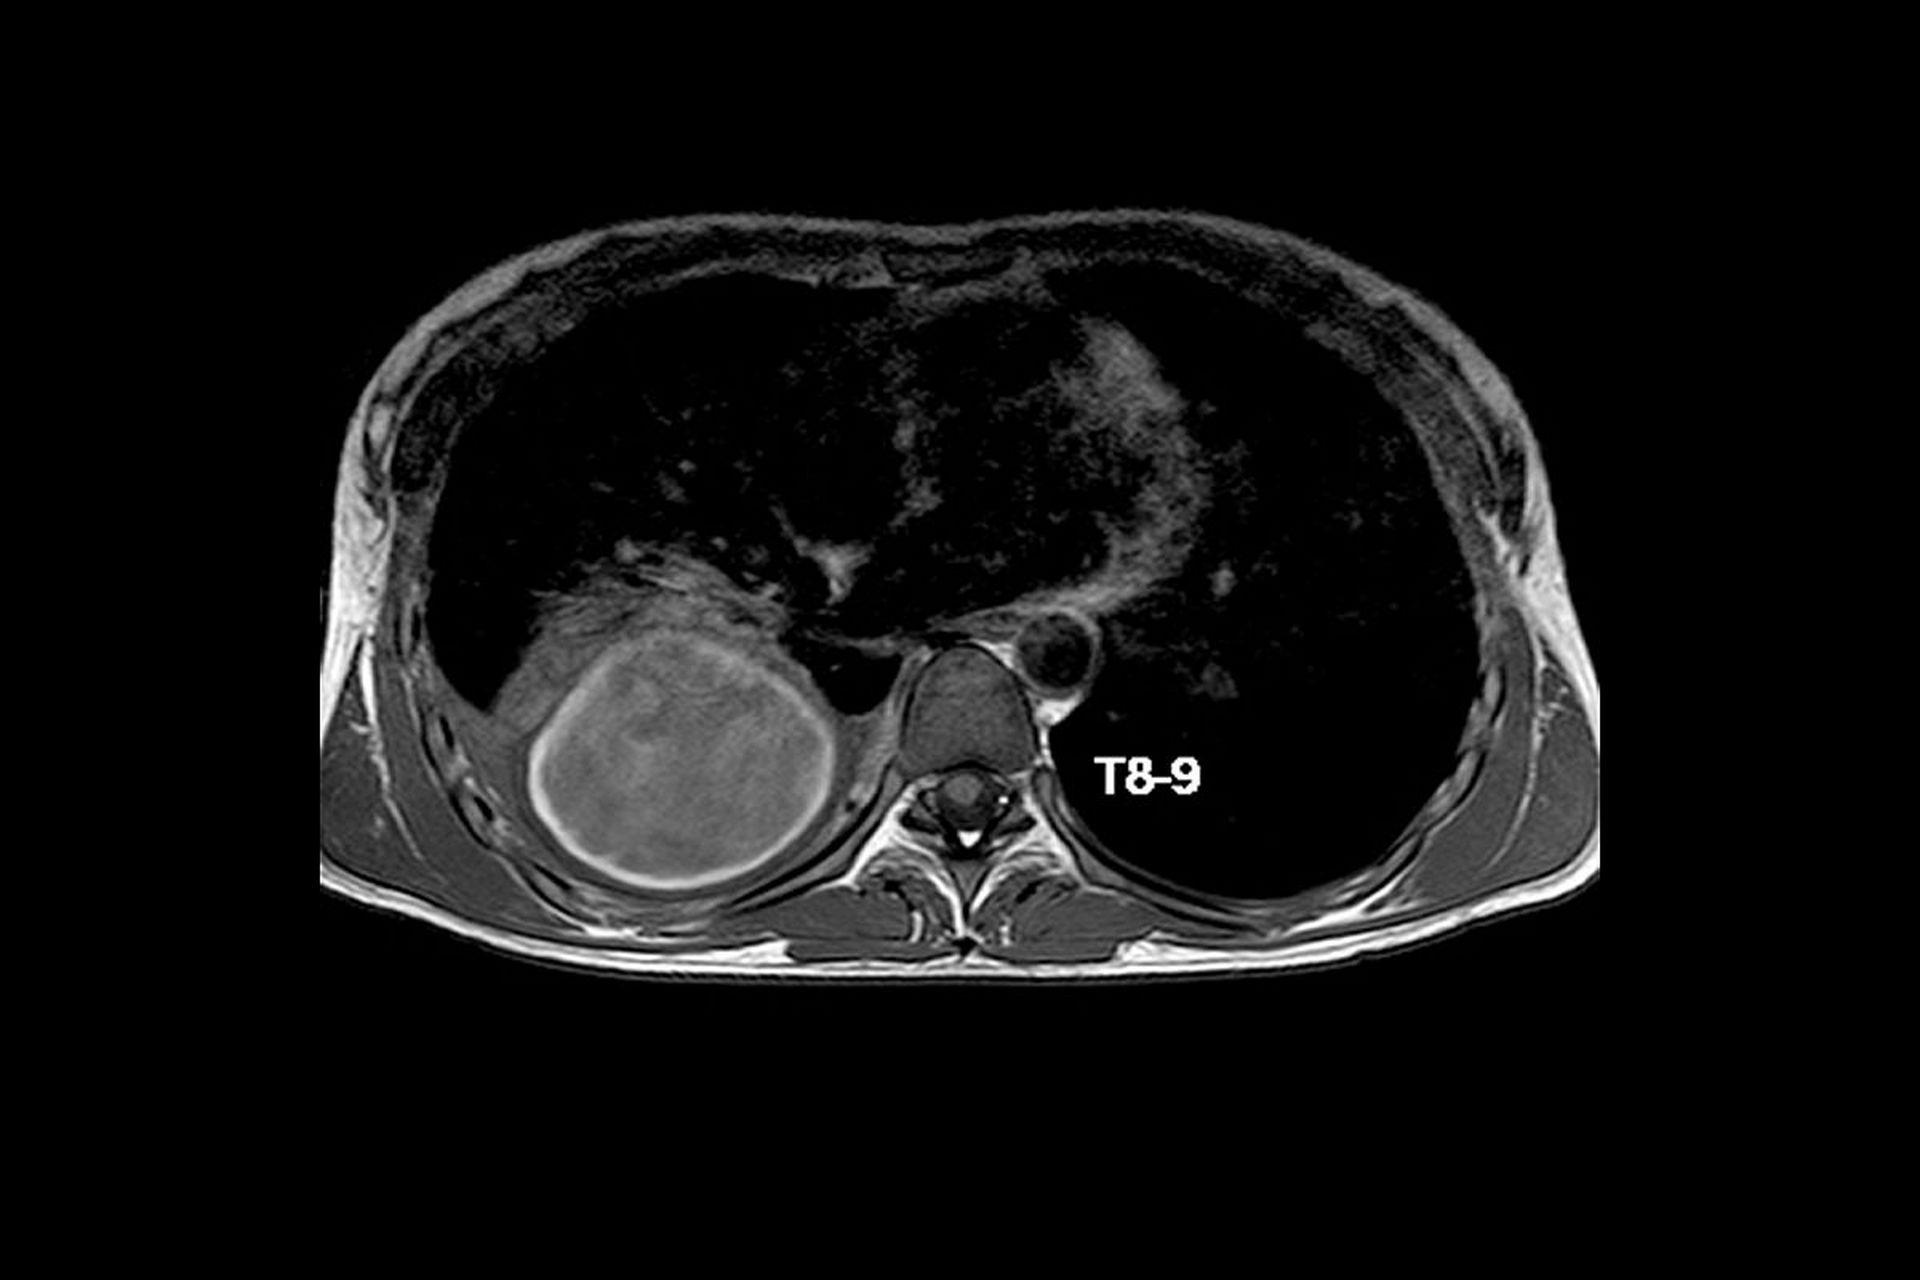

前后纵隔肿瘤一例

图片尺寸4032x3024